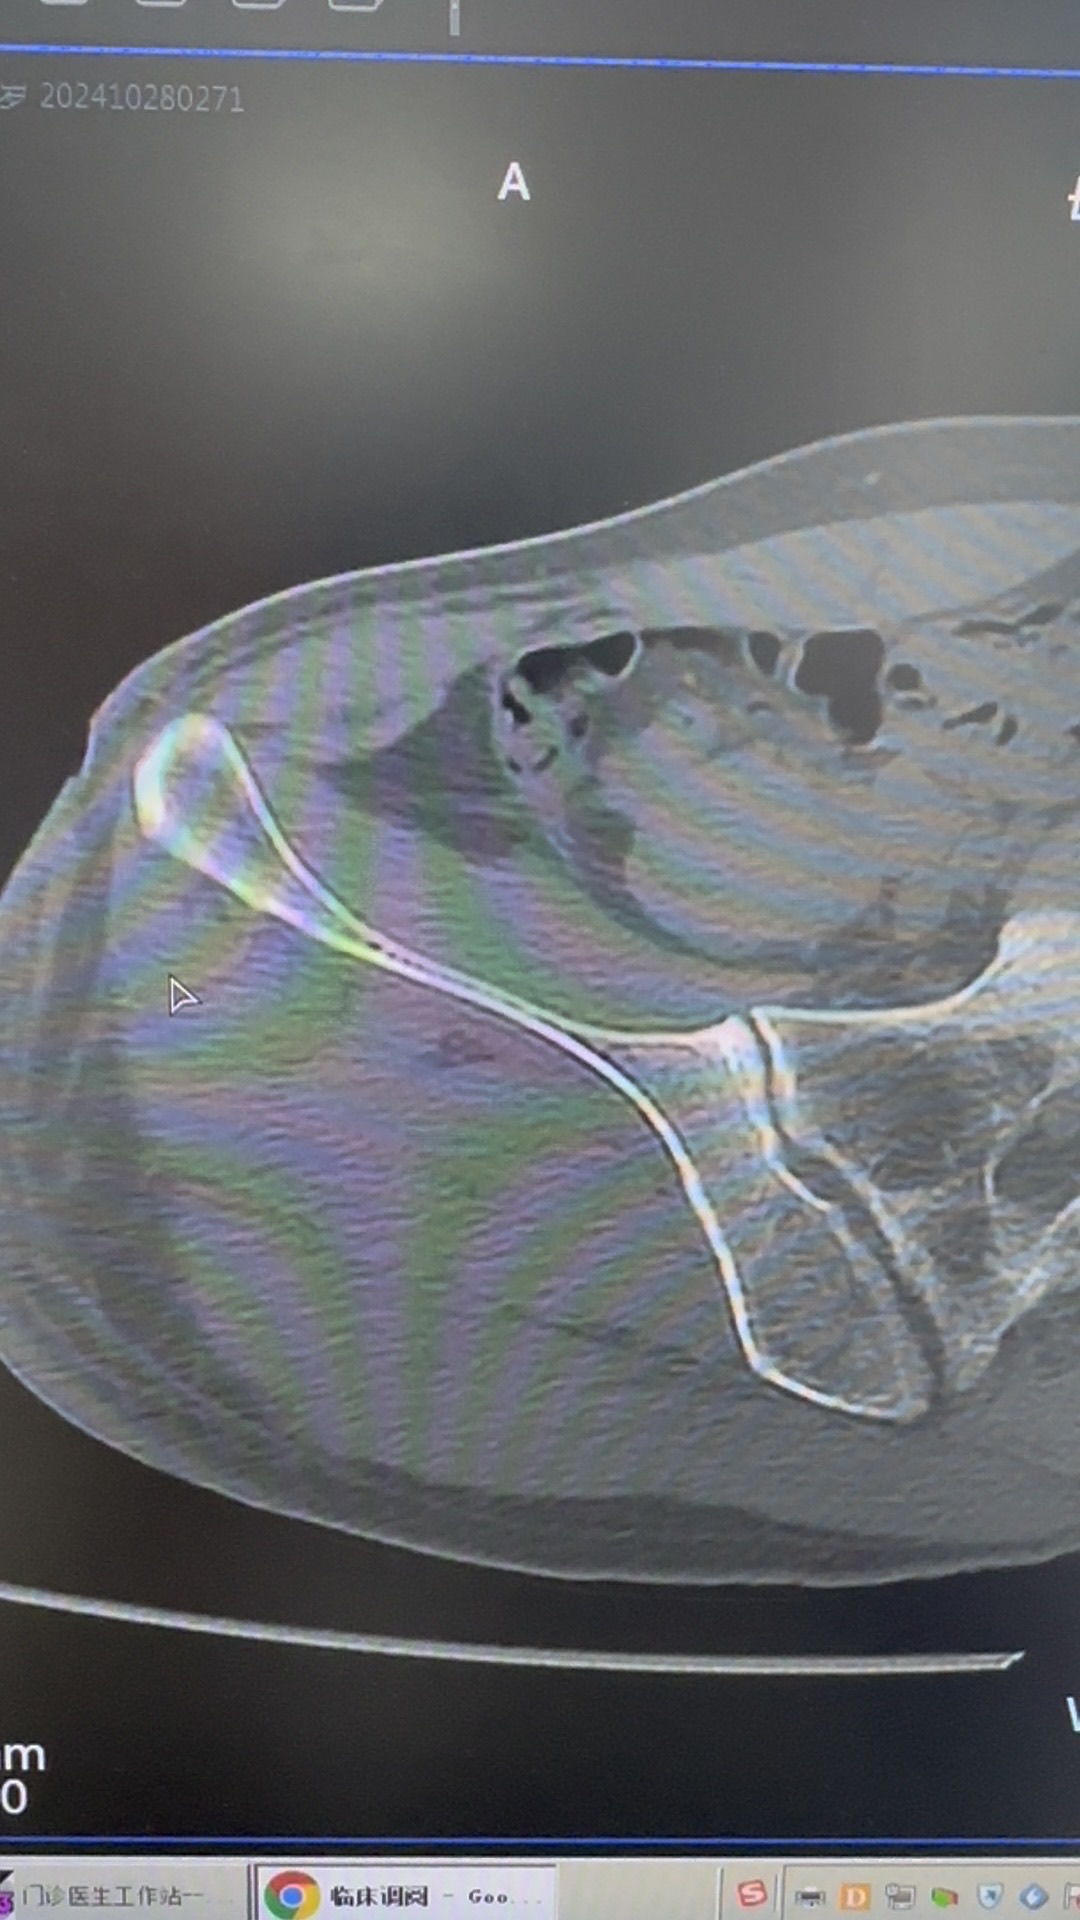

【患者信息】:51岁,男性,高处坠落伤

【主诉】:摔倒致右髋部肿痛活动受限2天入院

【临床诊断】:粗隆下骨折,seinsheimer Ⅴ型

【治疗经过及结果】:切开复位内固定